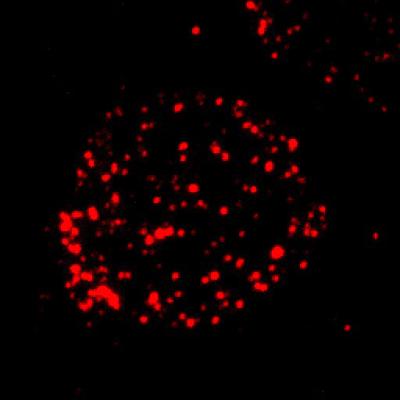

image: This image shows FCMR expression by immunofluorescence. view more

Credit: UAB